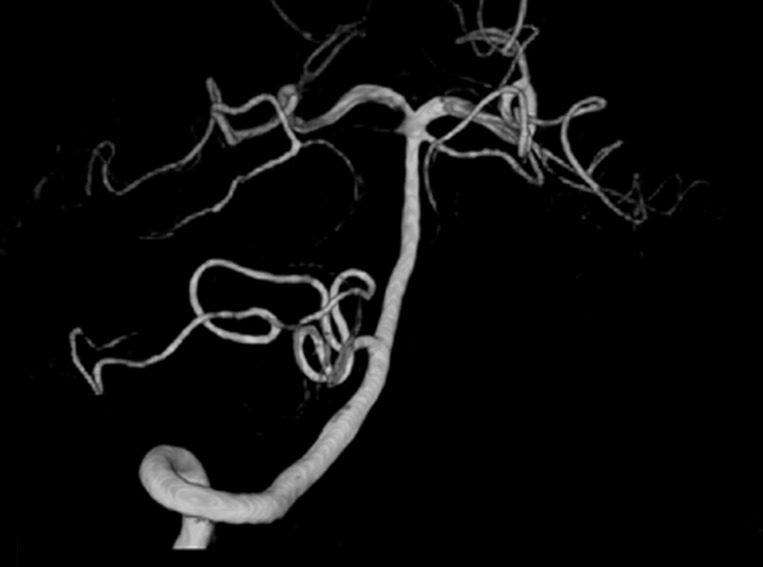

Fig. 1) or MR imaging of the brain were available, 2) results of CT angiography (CTA) or MR angiography (MRA) or 3-dimensional digital subtraction cerebral angiography (DSA) were available (

Fig. 2) to identify any intracranial aneurysm that might be present (

All eligible patients were categorized into 2 groups; aneurysmal SAH (A-SAH) and non-aneurysmal SAH (NA-SAH). The former group included those SAH patients with intracranial aneurysm detected by CTA and/or MRA and/or DSA. The technique and procedures of DSA have been described elsewhere [

Fig. 2Three-dimensional digital subtraction cerebral angiography (DSA) showing the normal posterior circulation artery, vertebral artery, basilar artery, posterior cerebral artery, and superior cerebellar artery.